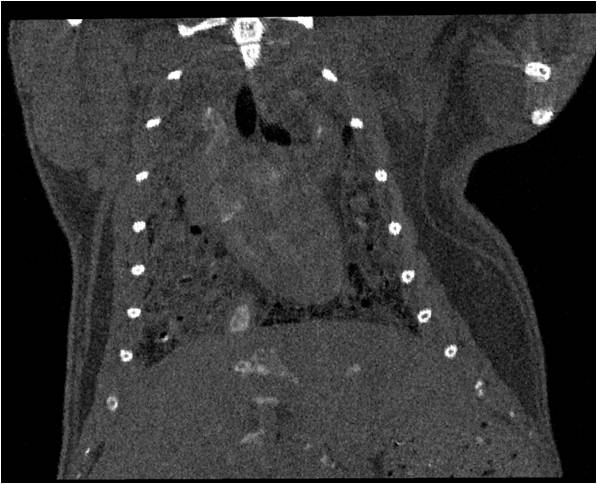

心血管

胸部和心血管的層析成像                                       胸部和心血管的3D圖像